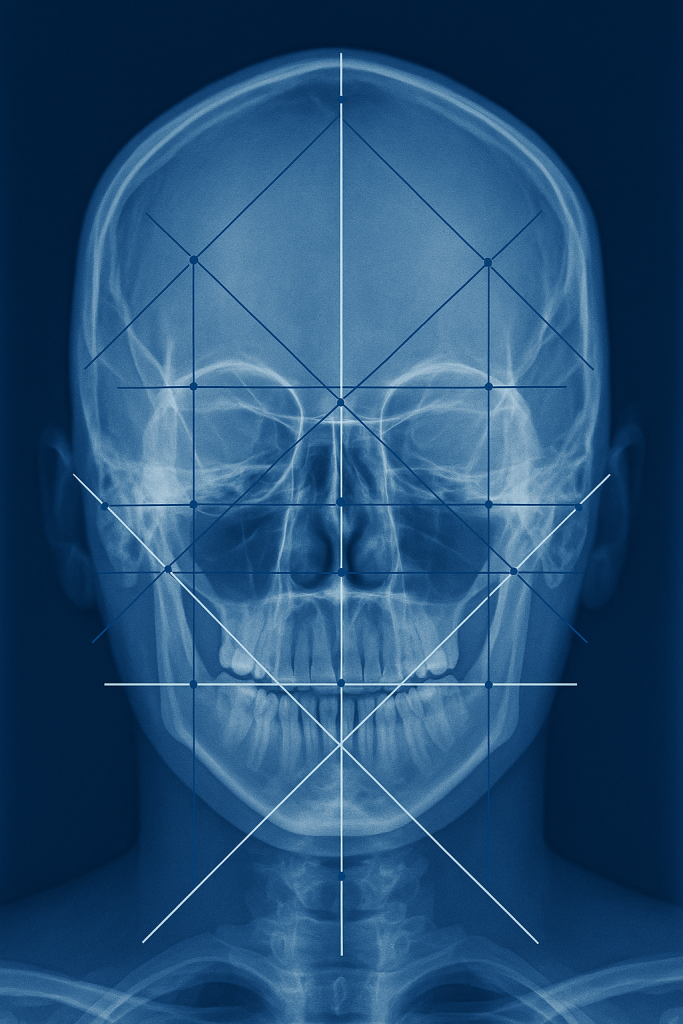

تحلیل سفالومتری یکی از مهمترین مراحل تشخیص در ارتودنسی است. اگر بخواهیم ساده توضیح دهیم، سفالومتری نوعی رادیوگرافی تخصصی از ناحیه سر و صورت است که به متخصص ارتودنسی این امکان را میدهد تا وضعیت استخوانها، فکها، دندانها و الگوی رشد صورت را دقیق بررسی کند.

این روش برای بیش از پنجاه سال یکی از پایههای اصلی برنامهریزی درمان ارتودنسی بوده و هنوز هم به دلیل دقت بالا و اطلاعات ارزشمندی که ارائه میکند، کاملاً ضروری است.

تحلیل سفالومتری (Cephalometric Analysis) مجموعهای از اندازهگیریها و ارزیابیهایی است که روی عکس سفالومتری انجام میشود.

این رادیوگرافی معمولاً از نمای پهلو (Lateral Cephalogram) گرفته میشود و گاهی نمای روبهرو نیز برای تکمیل بررسیها لازم است.

در این عکس، نقاط آناتومیک مشخصی توسط متخصص تعیین شده و بر اساس خطوط و زوایا تحلیل میشوند. این اطلاعات برای تشخیص دقیق و طراحی طرح درمان لازم است.

تحلیل سفالومتری چگونه انجام میشود؟

۱. گرفتن عکس سفالومتری

فرایند سریع، بدون درد و با اشعه کمتر از عکس پانورامیک است.

۲. علامتگذاری نقاط آناتومیک

نقاط خاصی روی عکس مشخص میشوند که مبنای اندازهگیری هستند.

۳. اندازهگیری زوایا و فواصل

زاویهها و خطوط مهمی مانند:

SNA

SNB

ANB

و شیب دندانهای بالا و پایین محاسبه میشود.

۴. تفسیر نهایی توسط ارتودنتیست

متخصص ارتودنسی با توجه به این دادهها، بهترین طرح درمان را انتخاب میکند.

تحلیل سفالومتری چه اطلاعاتی ارائه میدهد؟

۱. موقعیت فکها نسبت به جمجمه

تشخیص جلو یا عقب بودن فکها.

۲. زاویه و موقعیت دندانها

ارزیابی بیرونزدگی یا عقببودگی دندانها.

۳. نوع الگوی رشد صورت

عمودی، افقی یا طبیعی.

۴. هماهنگی اجزای صورت

بررسی تناسب لبها، بینی، چانه و پروفایل.

۵. تشخیص نیاز به جراحی فک یا درمان سادهتر